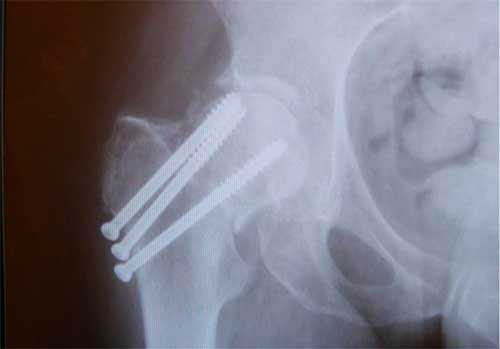

Остеосинтез ТБС на рентгене

При ПШБ в основном проводится внутренний (погружной) остеосинтез. То есть, специальная фиксирующая конструкция соединяется непосредственно с костными структурами после оперативного обнажения места перелома. В ортопедии применяют два вида внутреннего соединения репонированных отломков:

Интрамедуллярный метод

При интрамедуллярной технике дистальный и проксимальный отломки соединяются специальными стержнями или штифтами, проведенными через костномозговой канал каждого из них. Сегодня преимущество на стороне эндосистем блокирующего типа. На их противоположных концах имеются уже готовые отверстия для винтов или своеобразные загибы, повышающие степень стабилизации системы. Интрамедуллярными устройствами, которые бывают ригидными или полуэластичными, возможно зафиксировать даже множественные осколки.